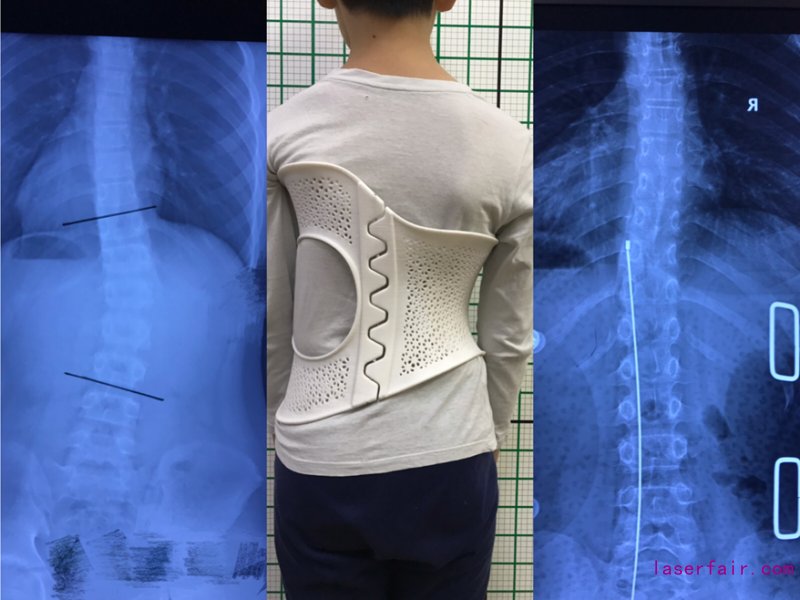

(側(ce) 彎30度,佩戴後調整到10度)

(側(ce) 彎25度,佩戴後矯正到7度)